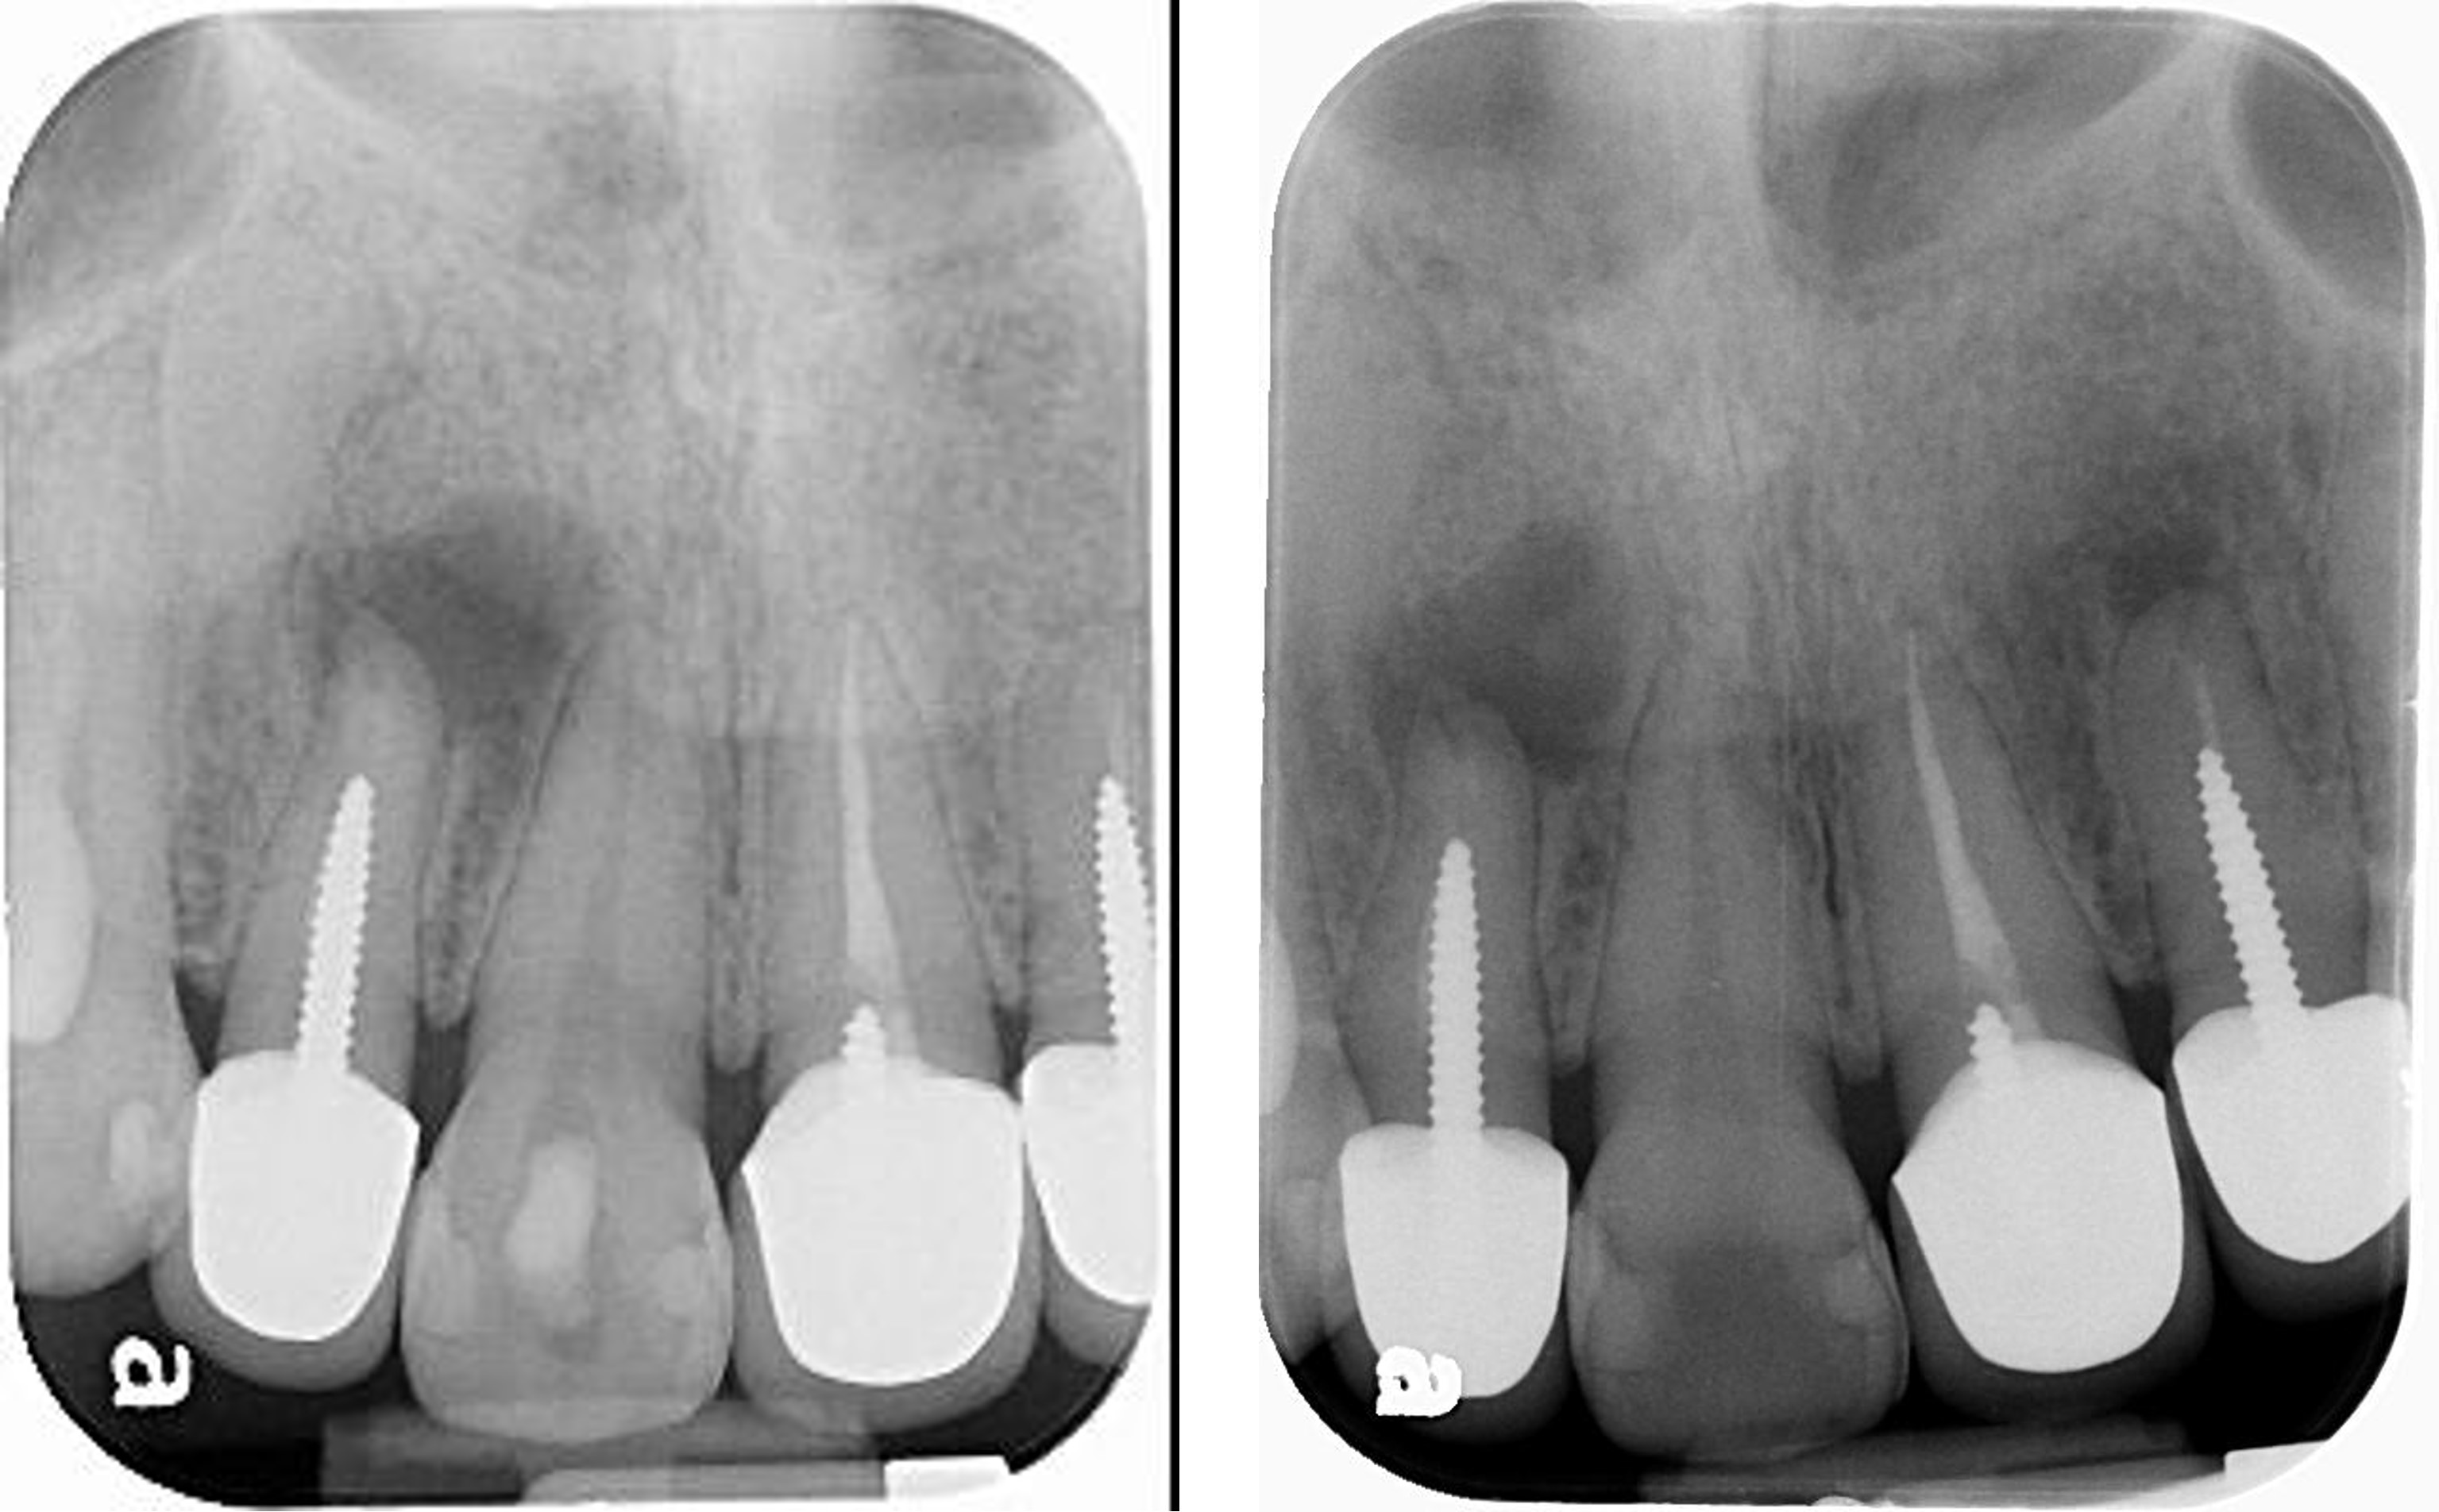

6個月後病變逐漸恢復

再6個月後,病變更消失

軟組織恢復更理想

根尖病變消失